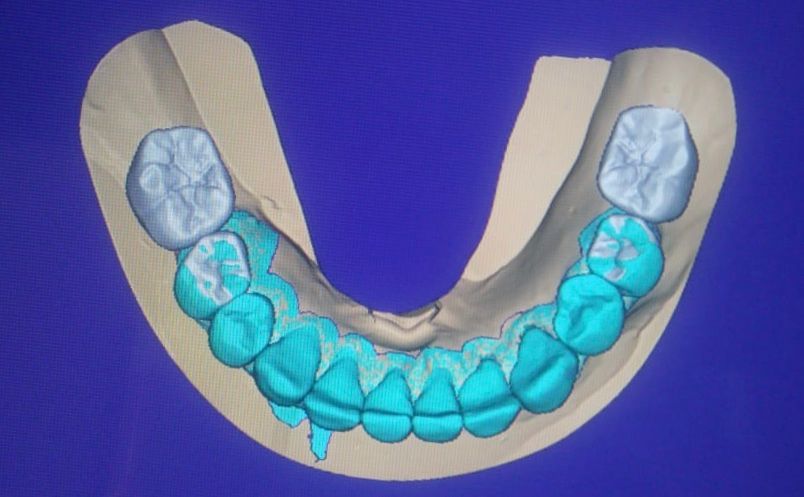

La especialidad en prótesis Bucal se enfoca en rehabilitar mediante prótesis unitarias, múltiples o totales la función masticatoria de nuestros pacientes brindándoles una mejor estética dental, confort, anatomía dental y función.

Contamos con tecnología de punta que nos facilitara el diagnostico y tratamiento de tu problema dental lo cual hará mas predecible el éxito a largo plazo.

• Rehabilitación bucal

• Prótesis dental